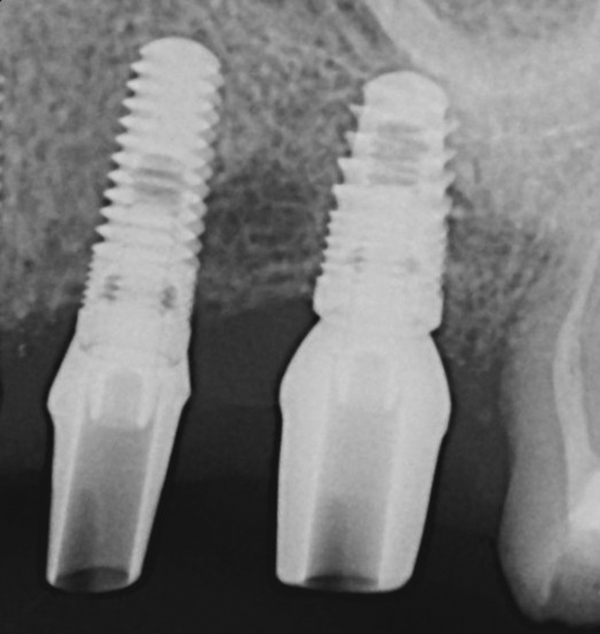

Subsequently, Trisi et al2 confirmed that increased insertion torque reduced implant micromotion when the implants were subjected to lateral forces in vitro (bovine bone). However, it was noted that this relationship may not always be true for all implant designs (Figure 3) and drilling techniques.61 For instance, compared with soft bone, there may be no benefit in increasing insertion torque in dense bone after stability is attained. One can surmise that a moderate increase of insertion torque may provide some benefits with respect to reducing micromotion, especially in less dense bone. However, the amount of increased force that is beneficial is unclear. Another technique to enhance initial stability is to use tapered implants, which develop elevated insertion torque forces. 14,62

Fig 3. Examples of implants with different thread designs. On the left is an implant with standard v-threads, and on the right is an implant with larger, more aggressive threads. The implant on the right was inserted with 20-Ncm-greater insertion torque than its counterpart.

Figure 3